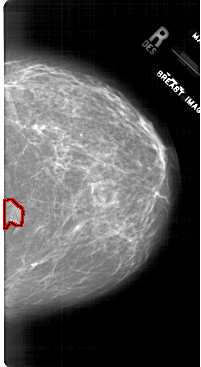

A_1745_1.RIGHT_CC

RIGHT_CC LINES 6601 PIXELS_PER_LINE 3601 BITS_PER_PIXEL 12 RESOLUTION 43.5 OVERLAY

FILE: A_1745_1.RIGHT_CC.OVERLAY

TOTAL_ABNORMALITIES 1

ABNORMALITY 1

LESION_TYPE MASS SHAPE IRREGULAR MARGINS ILL_DEFINED

ASSESSMENT 4

SUBTLETY 2

PATHOLOGY BENIGN

TOTAL_OUTLINES 1

BOUNDARY